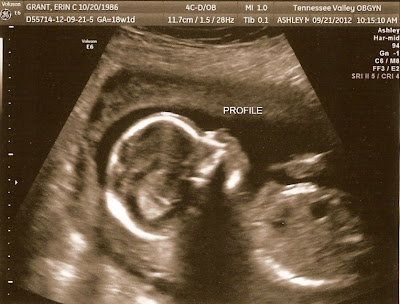

Also, here are our ultrasound pictures from last week…

![]() |

| It’s a girl! :) |

| View of her head and torso from the side |